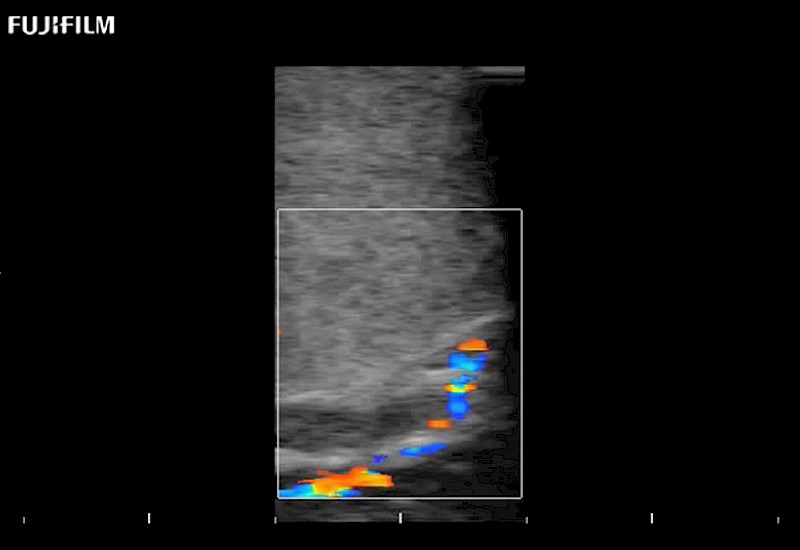

Exclusive 10mm side‐fire linear array transducer with 2.87mm diameter is ideal for real‐time visualization through and behind structures and instant, scalable definition of anatomy and vascularity including the ability to delineate and define tumor margins.

Main Specifications: